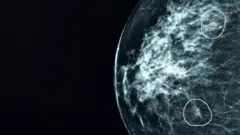

மருத்துவர்களால் பார்க்க முடியாத புற்றுநோய் கட்டிகளை கண்டறியும் 'மியா'